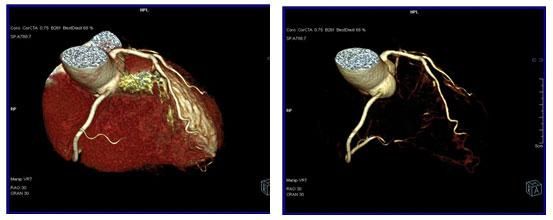

64排螺旋CT冠狀動脈血管成像:

1、簡單:無需經動脈插管,隻需象平時靜脈輸液一樣在肘靜脈内推注相對适量對比劑,然後行快速掃描即可完成整個檢查。

2、安全:64排螺旋CT冠狀動脈造影,對比劑用量較少,無需動脈插入導管,患者無需承擔麻醉及動脈插管等帶來并發症的危險。在冠狀動脈血管疾病的篩查、早期診斷、冠狀動脈成形術和搭橋術前、術後血管評價,冠狀動脈起源異常及心肌橋等方面極具優勢。

3、後處理功能豐富:西門子公司爲SOMATOM Definition AS+ 128層4D螺旋CT配備了功能強大的後處理工作站:MMWP(多産品工作站)和最新型的醫學影像IT工作平台,Syngo.via,智能,便捷。

CT冠脈血管成像:

1.冠脈軟斑塊:

2.混合性斑塊:

3.對于斑塊性質的确定,CT優于DSA: